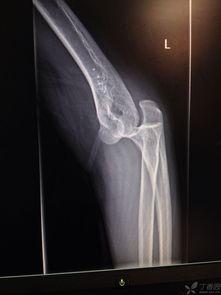

首先,得先弄明白什么是前臂脱臼。简单来说,就是你的前臂关节突然脱离了原来的位置,就像一个精密的机械突然出了故障。这种情况在日常生活中并不少见,比如摔倒、扭伤等。

那么,如何才能把脱臼的前臂复位呢?这就需要我们掌握一些专业的手法。下面,就让我带你一步步来学习这个神奇的复位法。